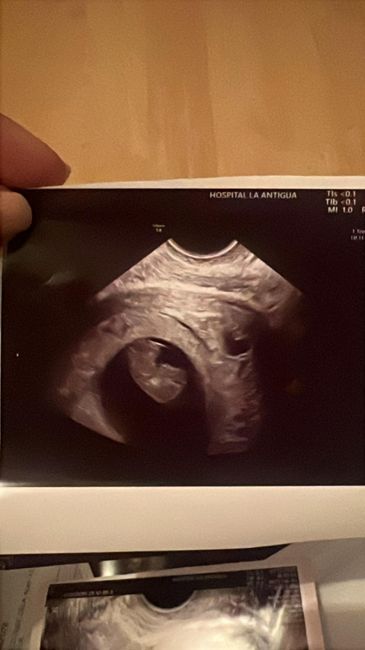

Hola! Me ayudáis por favor? Niño o niña? Es una eco en papel. Gracias!!!Método Ramzi 5